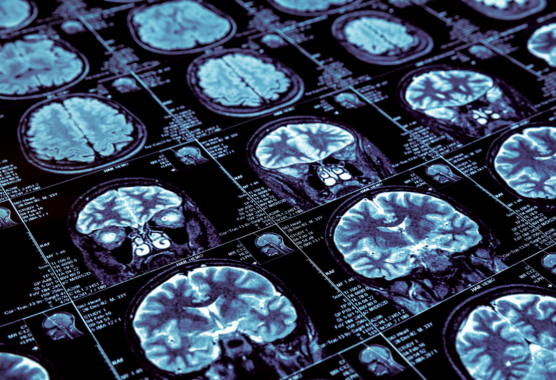

Orwa Aboud’s research focuses on glioma metabolism, neuro-oncology biomarkers, and the development of non-invasive diagnostic tools. His work integrates metabolomics and AI to uncover novel therapeutic targets and improve clinical outcomes for patients with brain tumors.